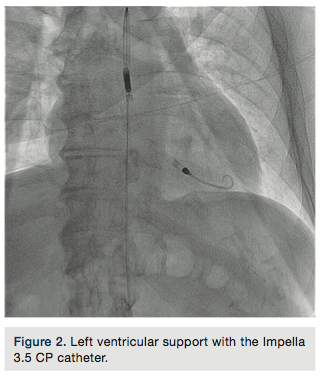

A 6 French (Fr) hydrophilic introducer sheath was placed in the right radial artery in a standard fashion. A 14Fr introducer sheath with a 3.5 Impella CP catheter was placed via the right femoral artery using micropuncture access, into the left ventricular cavity and left ventricular (LV) support was initiated (Figure 2). A 5Fr pulmonary artery (PA) catheter was placed via the right basilic vein and right heart pressures were measured. Therapeutic doses of unfractionated heparin were administered and an Impella anticoagulation protocol was followed.